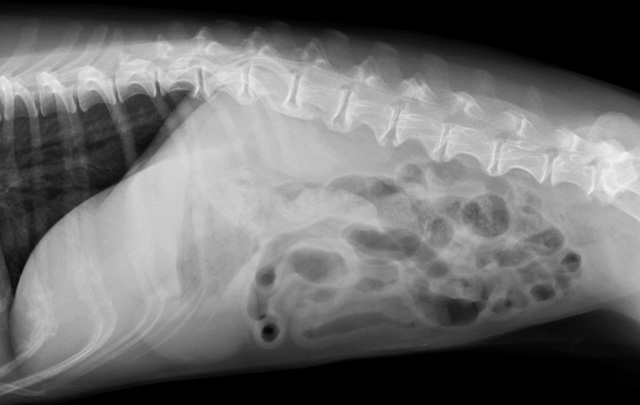

おもちゃや中毒物質を食べてしまった際、当院ではレントゲンやエコーで即座に位置を確認します。催吐処置(吐かせる処置)はもちろん、お腹を切らずに異物を摘出できる「内視鏡」や、緊急の外科手術にも柔軟に対応可能です。

猫ちゃんは毛糸や紐を好んで飲み込みますが、これは非常に危険です。紐が腸に引っかかると、短時間で腸に穴が開く(穿孔)恐れがあります。当院では迅速な画像診断を行い、手遅れになる前の早期外科摘出を徹底しています。

糞便検査で寄生虫や菌を確認し、必要に応じてエコーやレントゲンでお腹の中を可視化します。